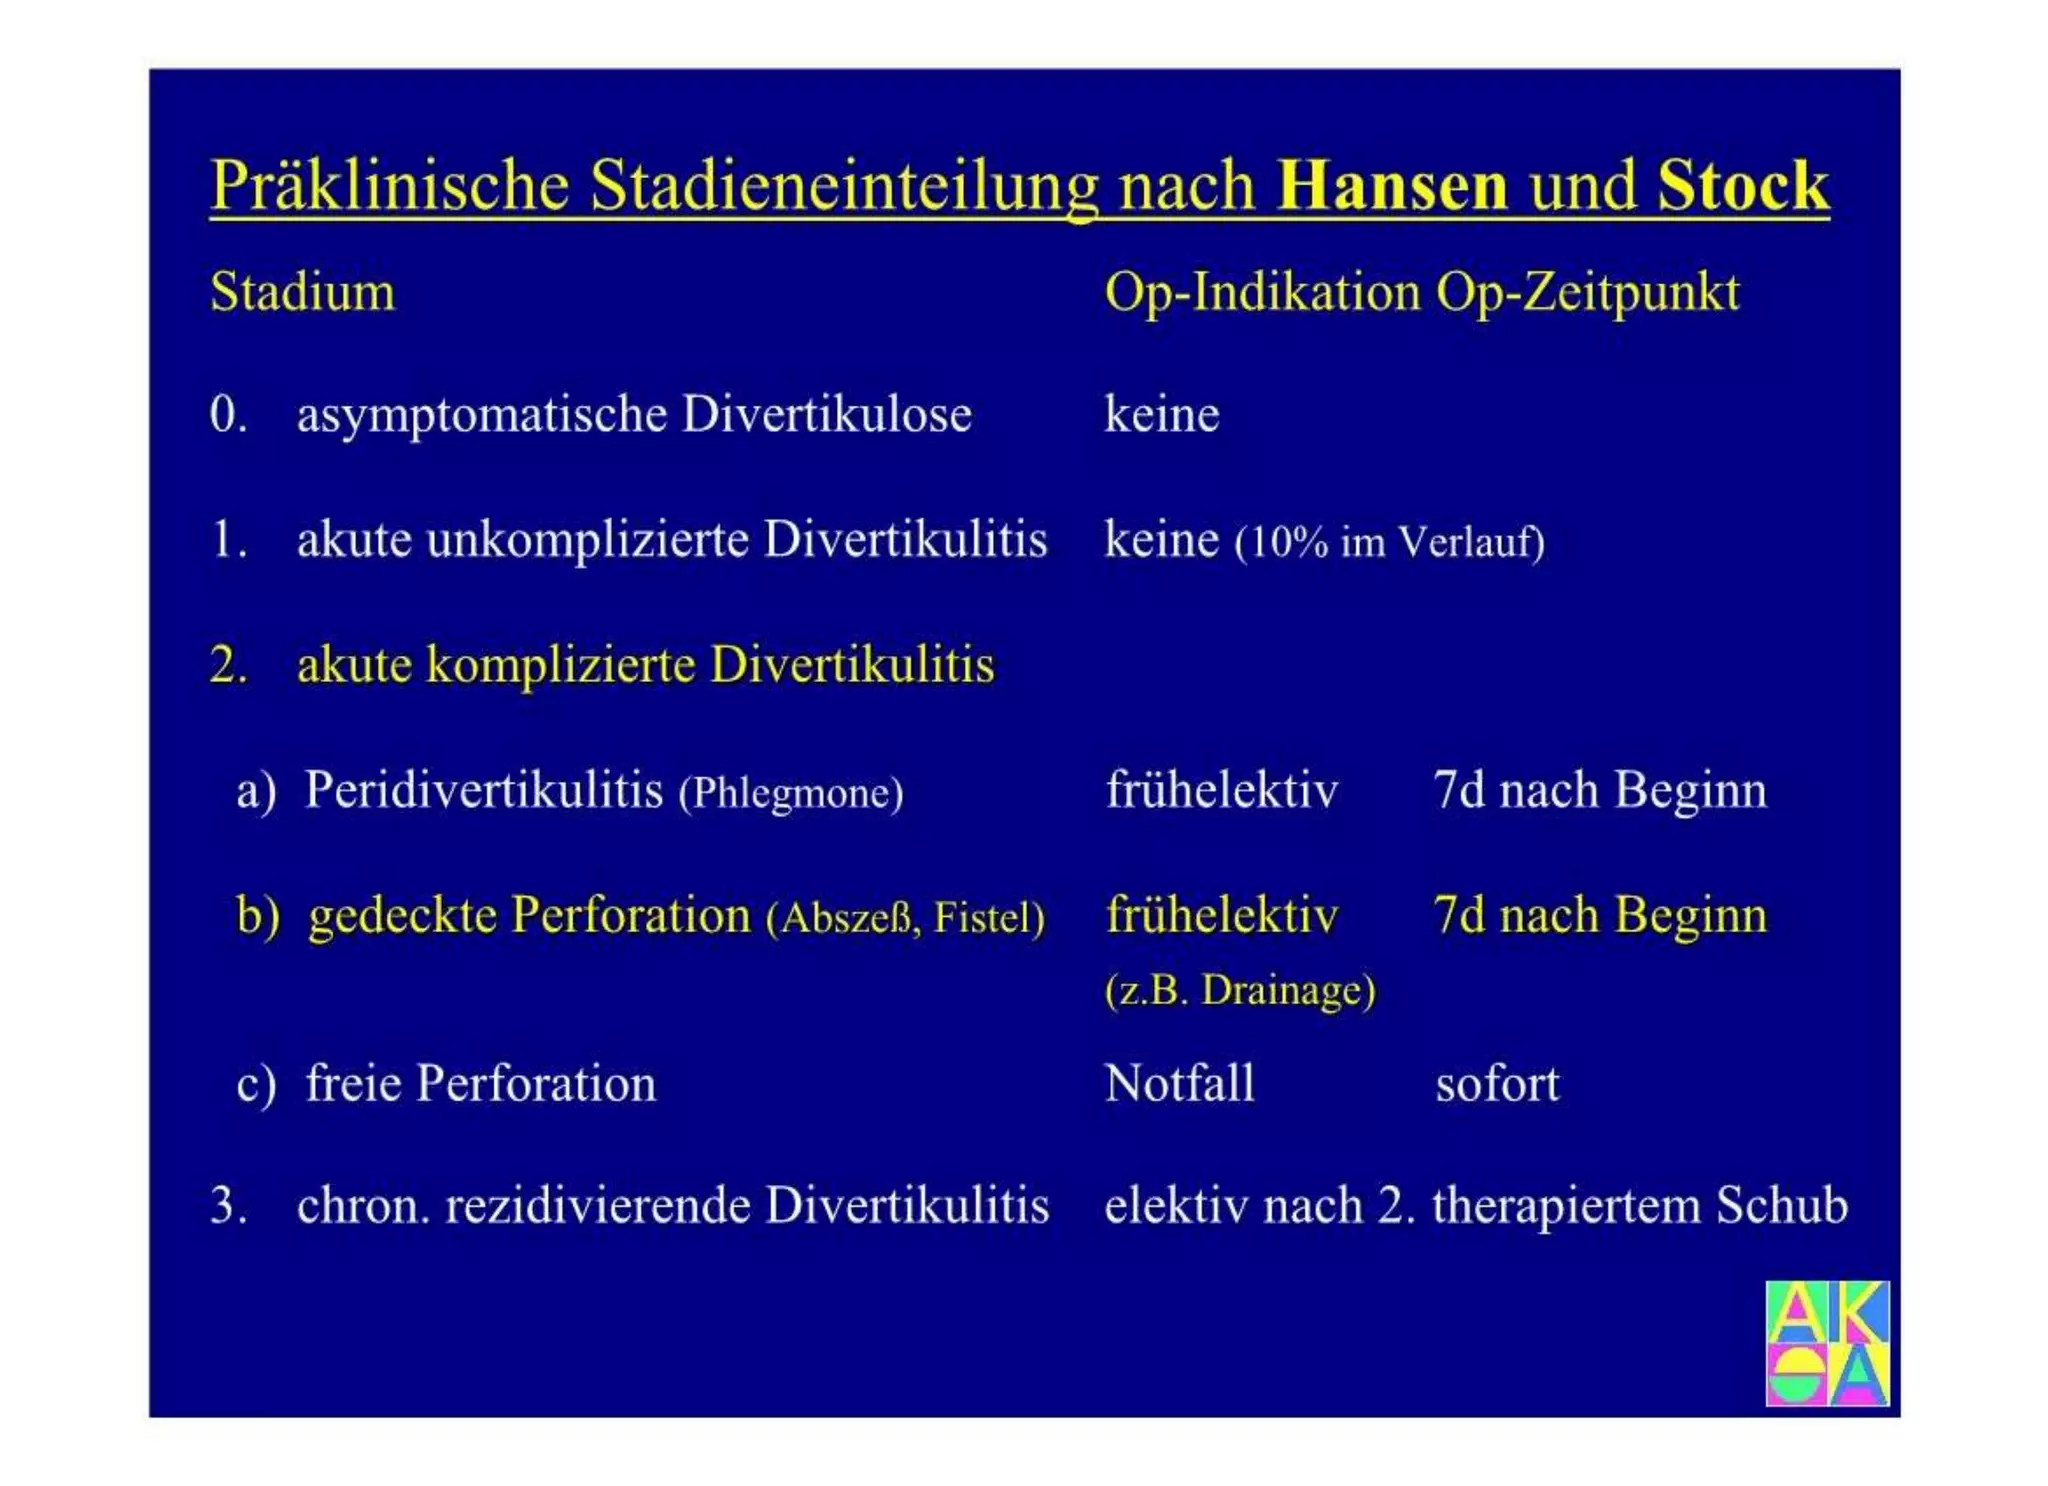

Chronische Enteropathie und Ileus, Dünndarm und Dickdarmdiagnostik, Mechanischer und paralytischer Ileus, Eingeklemmte Darmabschnitte, aufgereihter Bridenileus, und dazu Dickdarmileus, eingeklemmte Hernien, Weitergabeskript